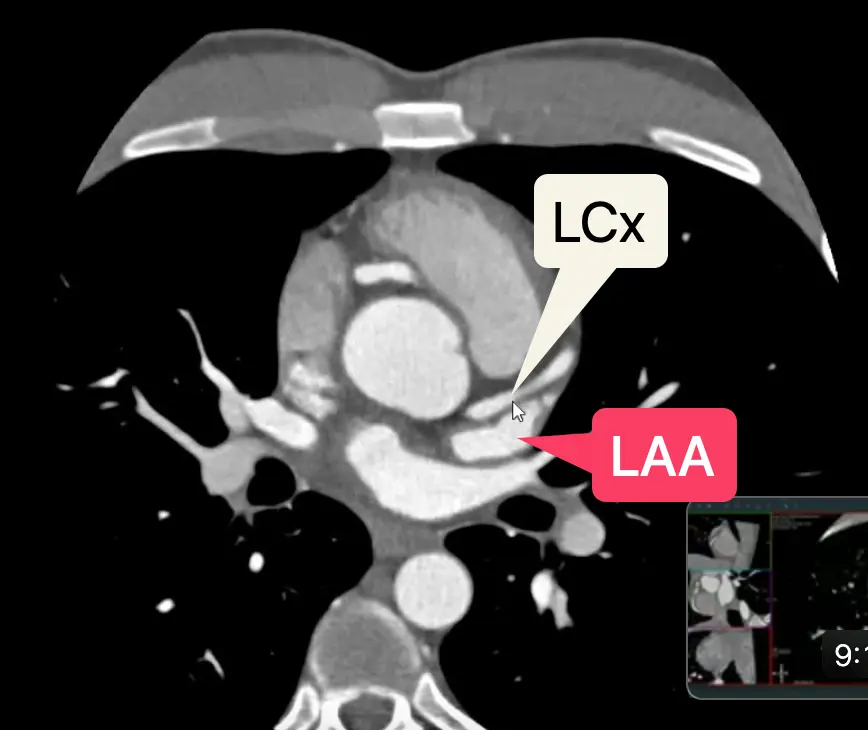

- LCx

- Reset your view and line up 2 orthogonal views → visualize SAX view

- By definition, the LCx travels within the L atrioventricular groove, which will course below the LAA.

- In some patients, you may see a small caliber “true” LCx (which you’ll know b/c it travels along the L AV groove) and a dominant OM, which appears large/beefier by comparison.

- You may appreciate the SA nodal branch, which arises off of the proximal LCx and extends to the atrial septum

Left Atrial Appendage

- Open your 2-chamber (2CH) view (aka vertical long axis/VLA)

- Also provides a different view to assess the MV leaflets

- Scroll through to assess for any filling defect